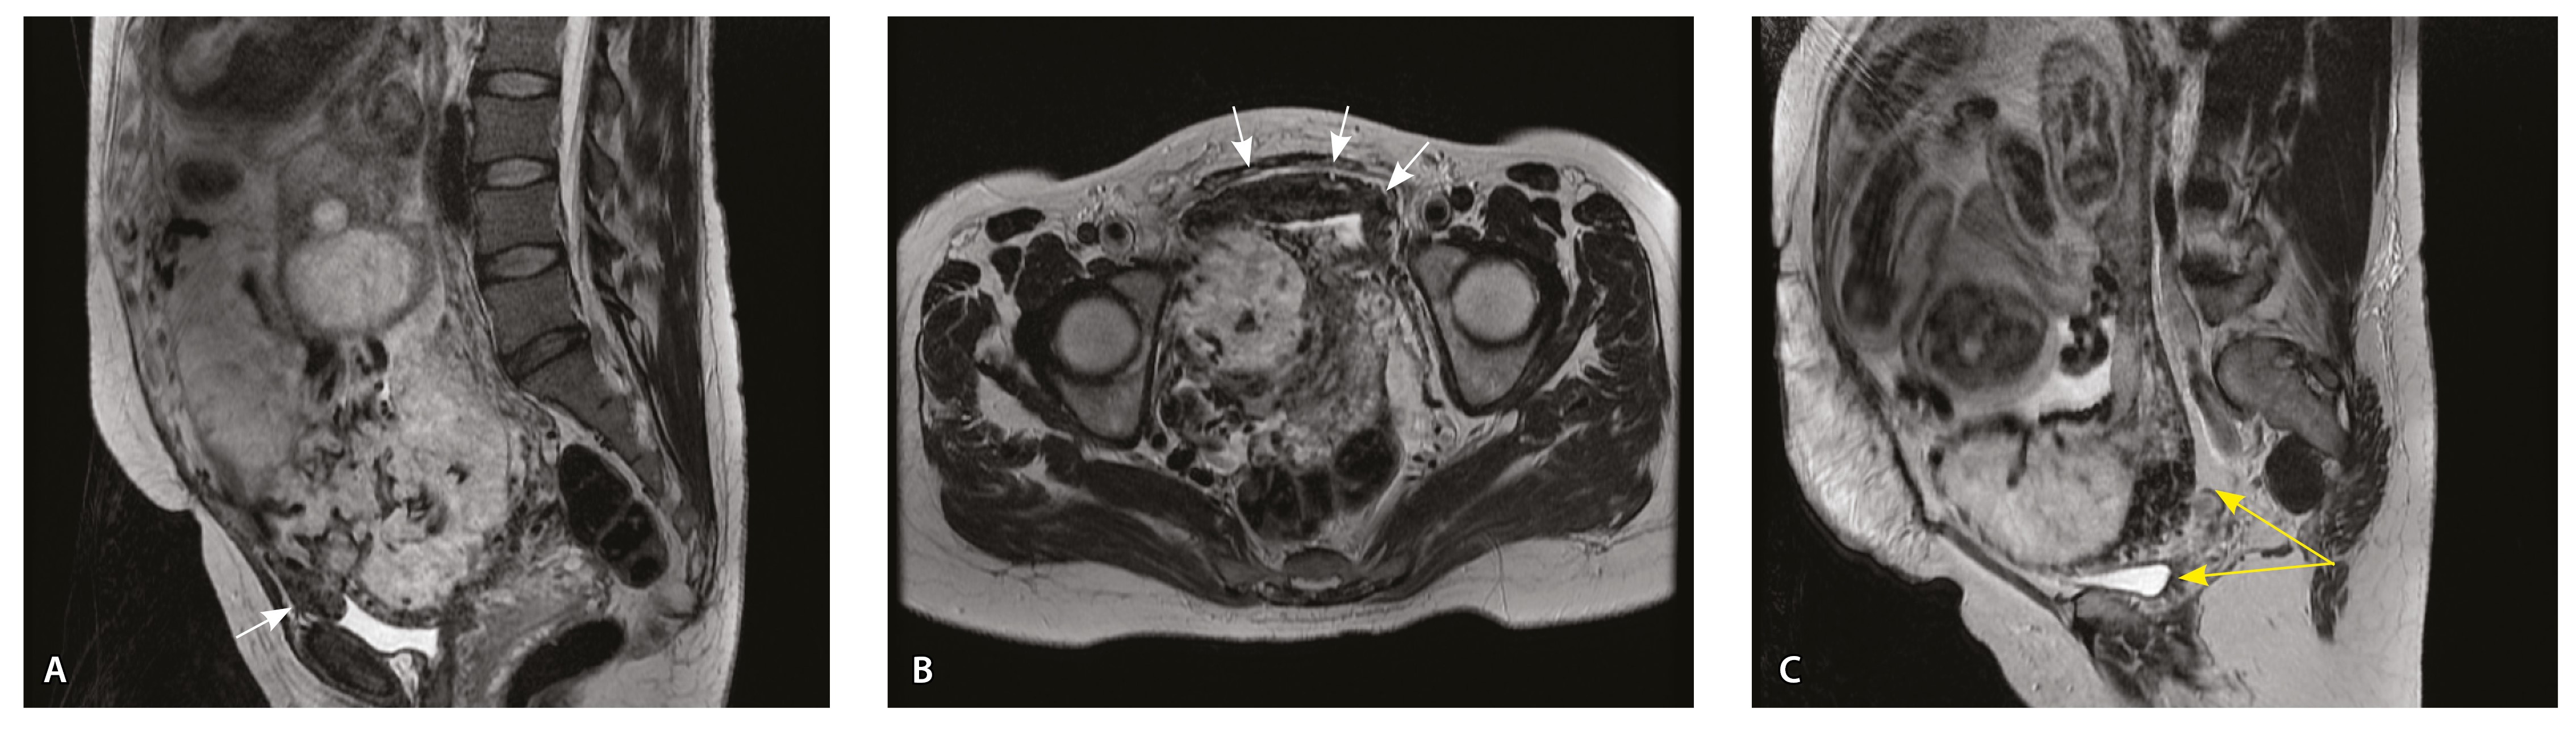

Сосуды 5-го типа. Наличие гиперваскуляризации за пределами матки по данным МРТ, на границе с мочевым пузырем с вовлечением его стенки, сосуды в области перешейка матки, параметрия, в том числе в сочетании с признаками фиброза, наличием рубцово-спаечных изменений и др. Можно предположить, что сосуды 5-го типа являются аналогом pl. рercreta PAS 3b, 3c (рис. 15).

Рис. 15. Беременность 34 недели, pl. percreta, PAS 3b по FIGO (A, Б), PAS 3c по FIGO (В). На магнитно-резонансных томограммах в режиме Т2-взвешенного изображения в сагиттальной (A, В) и аксиальной (Б) плоскостях определяется гиперваскуляризация в области выраженно истонченного нижнего маточного сегмента с распространением сосудов на заднюю стенку мочевого пузыря в области дна (белые стрелки), в область перешейка матки (желтые стрелки)

Данный вариант в патоморфологической картине наиболее сложен для оценки ввиду того, что такие структуры, как параметрий, перешеек матки, стенка мочевого пузыря, обычно не предоставляются в виде макропрепаратов, поэтому визуальные методы, в частности МРТ, могут с большей точностью оценить вовлеченность смежных структур. На микропрепаратах данный вариант инвазии плаценты сочетается с рубцово-спаечными изменениями задней стенки мочевого пузыря с нижним маточным сегментом (рис. 16).